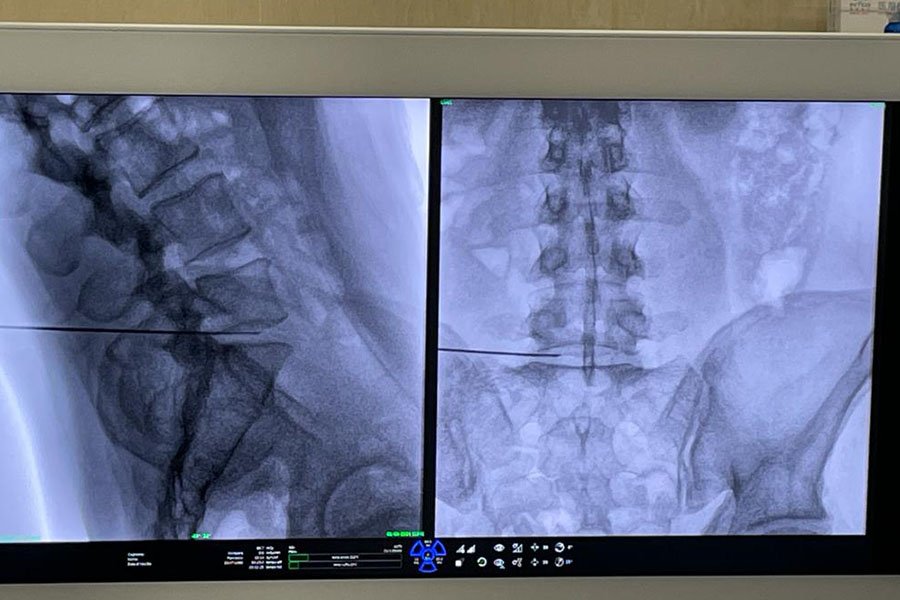

- Nucleolisi discale con ozono: prevede l’iniezione, in anestesia locale e sotto controllo radiologico, di ozono medicale all’interno del disco vertebrale da trattare